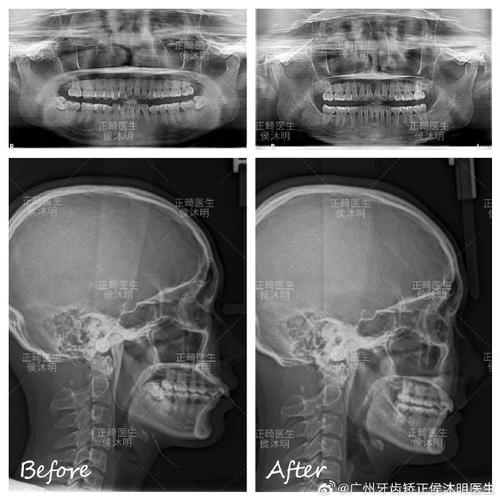

在临床应用中,PP平面与MP平面的关系主要通过“PP-MP角”来体现,即两平面在颅底平面(FH平面)上的夹角,该角度的正常范围约为20°-25°,若角度增大,提示上下颌骨垂直向不调,可能伴随下颌平面角增大(高角病例);若角度减小,则可能为垂直向骨性反颌或短面型,通过测量PP平面与MP平面分别到特定牙齿的距离(如上颌第一磨牙牙尖到PP平面的距离、下颌第一磨牙牙尖到MP平面的距离),可评估牙齿的垂直向萌出状态,指导正畸治疗中的压低或伸长设计。